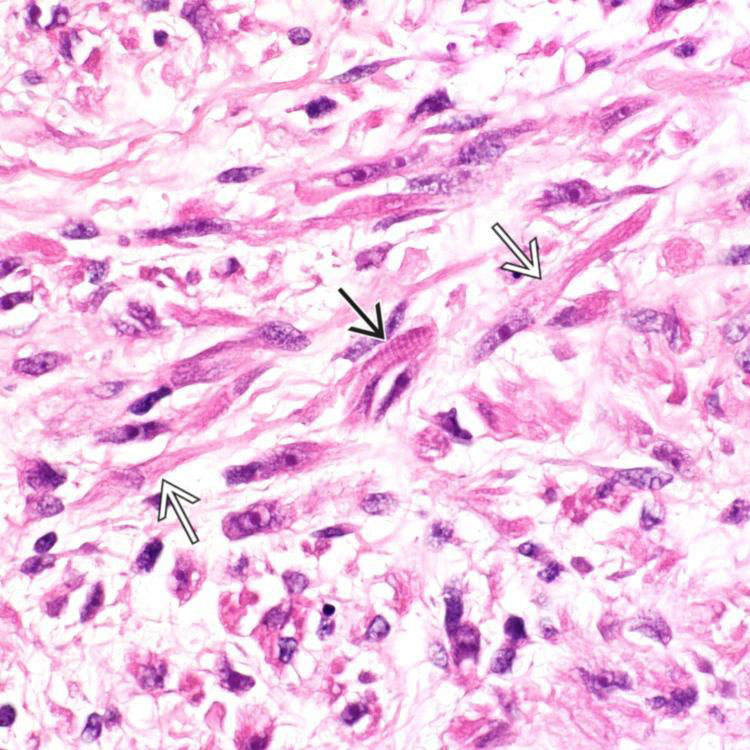

Embryonal Rhabdomyosarcoma Of The Orbit. A Diffuse Infiltrate Of

embryonal rhabdomyosarcoma strap cells cell cross striations focal cytoplasm eosinophilic elongated rms abundant multiple shows case area